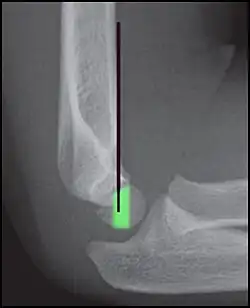

Anterior humeral line (black line), with normal area passed on the capitulum of the humerus colored in green in a 4-year-old child.[9] -

The anterior humeral line is not reliable in children with sparse ossification of the capitulum, such as in this 6 months old child.[9]

Anterior humeral line - It is a line drawn down along the front of the humerus on the lateral view and it should pass through the middle third of the capitulum of the humerus.[9] If it passes through the anterior third of the capitulum, it indicates the posterior displacement of distal fragment.[8]